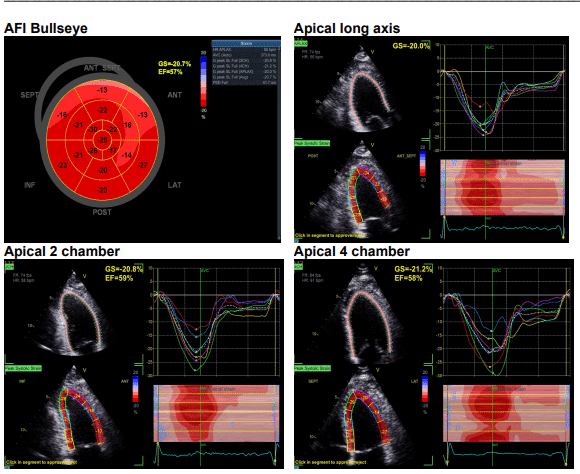

• analyse des déformations cardiaques (strain).

• fonction ventriculaire systolique;